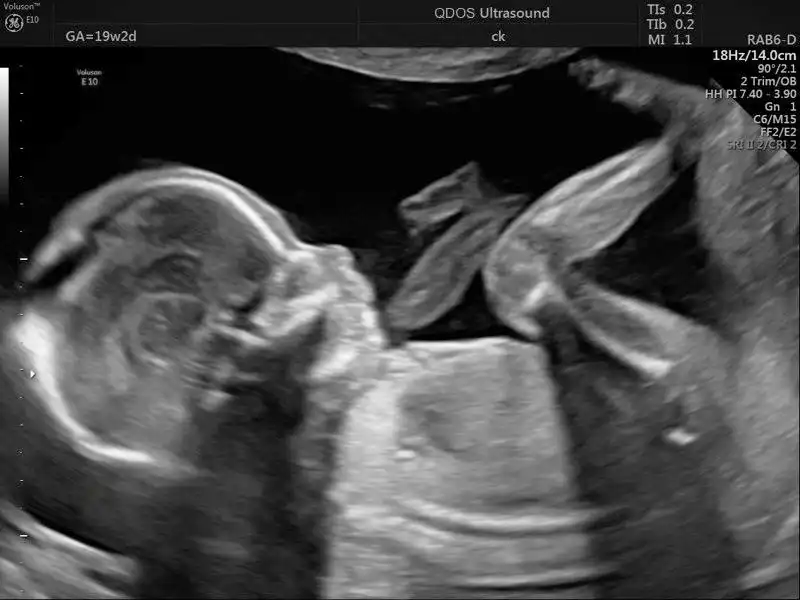

The woman, a resident of Songyuan city in Jilin province, is currently six months pregnant. Her pregnancy journey has been shared on social media through videos posted by her younger sister, who documents the day-to-day experiences of the elderly expectant mother. In the clips, the woman appears calm and optimistic as she speaks about feeling foetal movements and adapting to pregnancy at an advanced age.

According to accounts shared online, the woman lost her son in early 2025. While details surrounding his death remain undisclosed, she later opted for IVF, marking only the second pregnancy of her life. In one video, she shared that the baby becomes more active when she eats sweet food, leading her to believe the child may be a boy — a belief she associates emotionally with her late son.

Medical experts have raised serious concerns over pregnancies at such an advanced age. Doctors have warned that elderly pregnancies carry significantly higher risks, including complications that often require caesarean delivery and intensive medical supervision. Due to these risks, the woman undergoes frequent prenatal check-ups and travels long distances to major hospitals for specialised care.